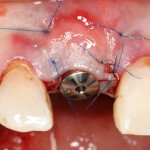

Устанавливаем имплантат XiVE (Dentsply Implants):

Сразу на имплантат — временная коронка:

которая через три месяца, к моменту интеграции импланта, выглядит совсем иначе: